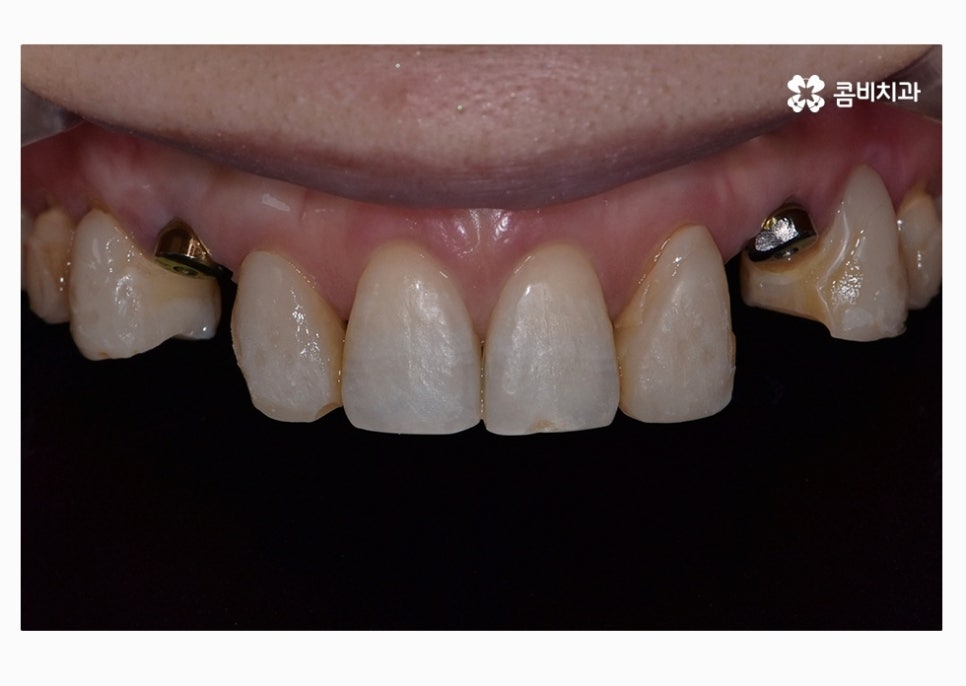

앞니의 경우 심미적으로 중요하기 때문에 임플란트

치료에 있어서 식립 각도부터 보철물의 모양, 색 등

정확해야 하고 연세가 많은 분들의 경우에는

주변 치아의 색과 모양에 맞는 보철물을 결합하여

마무리가 된다고 할 수 있어요.